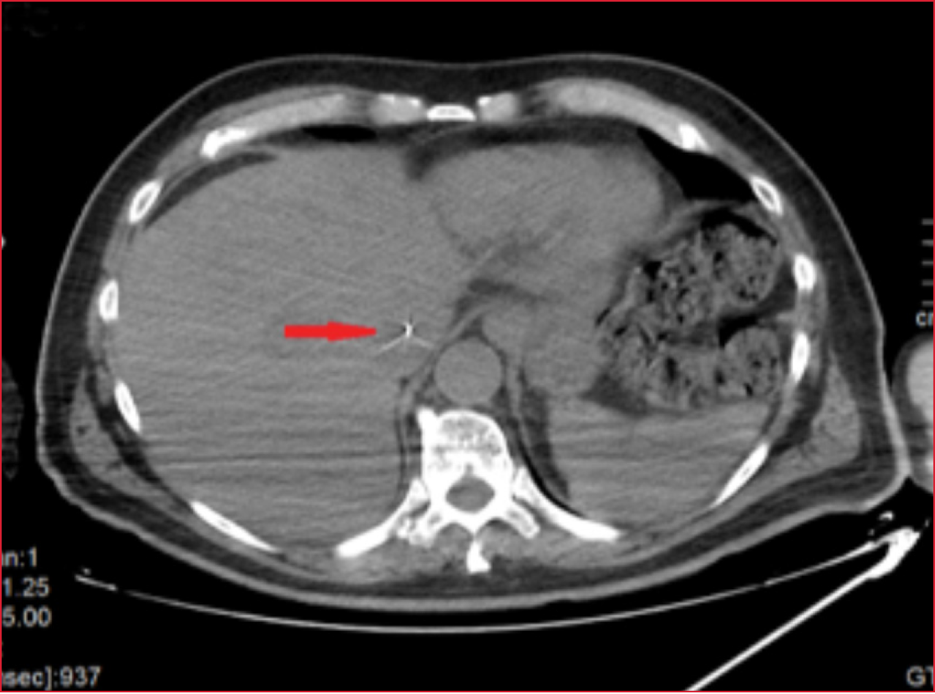

Paciente de 75 años, en el que se procedió a canalización de catéter venoso central de acceso periférico, con dificultad, con perdida de la guía metálica en el interior de la vena basílica. Se realizó radiografía de tórax, donde se objetivó la guía metálica llegando hasta la cava superior (Figura 1, flechas rojas) Se completó el estudio con tomografía computarizada, observándose progresión de la guía hasta la cava inferior, tanto en corte coronal (Figura 2, flecha roja) como en la vista axial (Figura 3, flecha roja). Se comentó el caso con Cirugía Vascular, que procedió a disección y venotomía basílica y extracción de guía sin complicaciones.